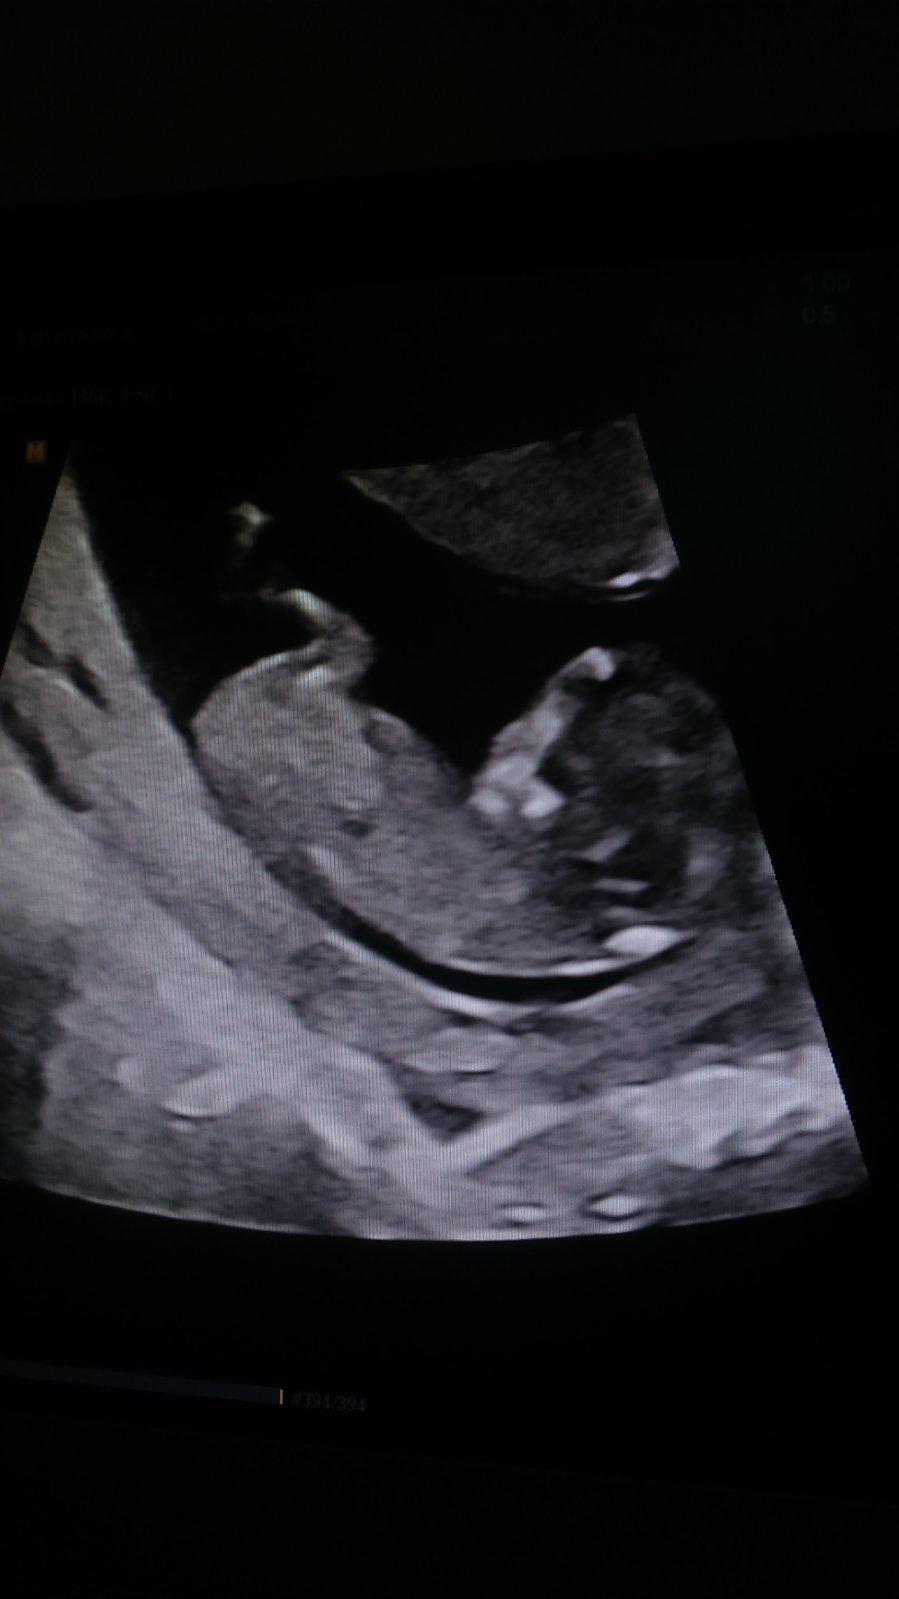

Tak už sa konečne môžem pochváliť novou fotkou drobca. Má približne 5,3cm a keď ho zobudili tak to vyzeralo akoby sa riadne rozčuloval, takže s ním určite bude veselo 🙂 tehotenskú knižku stále nemám, dá mi ju až o 4 týždne na ďalšej poradni aj s výsledkami z krvi. Na moje naliehanie mi dr vystavila papier ako potvrdenie pre zamestnávateľa, takže už aspoň môžem oznámiť.